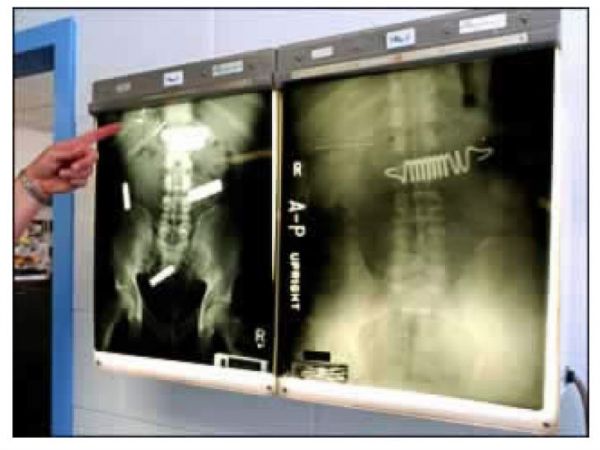

А так выглядит снимок человека, который проглотил немалое количество наркотиков, чтобы перевезти их контрабандой через границу.

Некоторые заключенные готовы проглотить все что угодно, лишь бы выбраться из тюрьмы, например, в больницу — даже пружины от матраса.